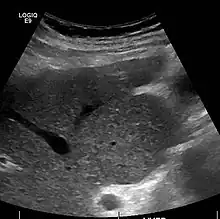

Ultrasound is routinely used in the evaluation of cirrhosis.[45] It may show a small and shrunken liver in advanced disease. On ultrasound, there is increased echogenicity with irregular appearing areas.[64] Other suggestive findings are an enlarged caudate lobe, liver surface nodularity[65] widening of the fissures and enlargement of the spleen.[66] An enlarged spleen, which normally measures less than 11–12 cm (4.3–4.7 in) in adults, may suggest underlying portal hypertension.[67] Ultrasound may also screen for hepatocellular carcinoma and portal hypertension.[45] This is done by assessing flow in the hepatic vein.[68] An increased portal vein pulsatility may be seen. However, this may be a sign of elevated right atrial pressure.[69] Portal vein pulsatility are usually measured by a pulsatility indices (PI).[68] A number above a certain values indicates cirrhosis (see table below).